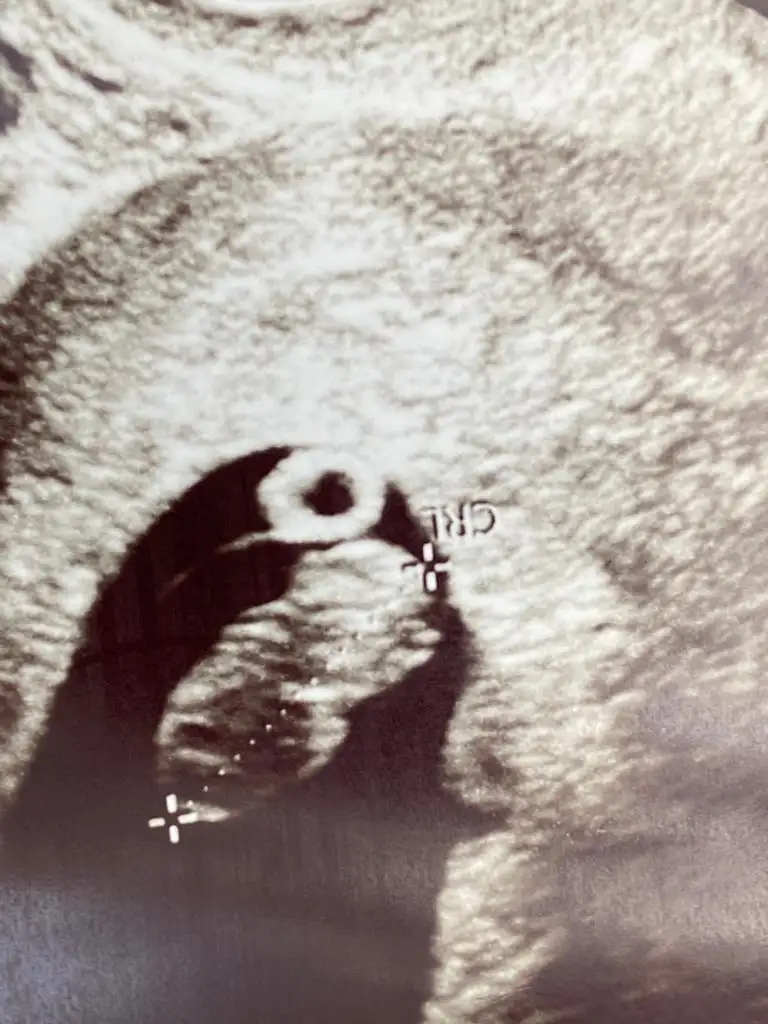

Canım benim 7. Gün 51,32 idi 9. Gün ise 99,2 idi Bugun kalp atışını duyduk maşşalah çok sağlıklıHayırlı akşamlar kızlar 24 nisanda 5.gün embriyosu transferim, pazartesi kan 50,53 bugün ise 99,12 iyi mi sizce artış

Siz de keseyle birlikte kalp atışını öğrendiniz dimiCanım benim 7. Gün 51,32 idi 9. Gün ise 99,2 idi Bugun kalp atışını duyduk maşşalah çok sağlıklı

Merhaba beta kaç bendeyken duydunuz acaba tebrik ederim bu arada maşallahCanım benim 7. Gün 51,32 idi 9. Gün ise 99,2 idi Bugun kalp atışını duyduk maşşalah çok sağlıklı